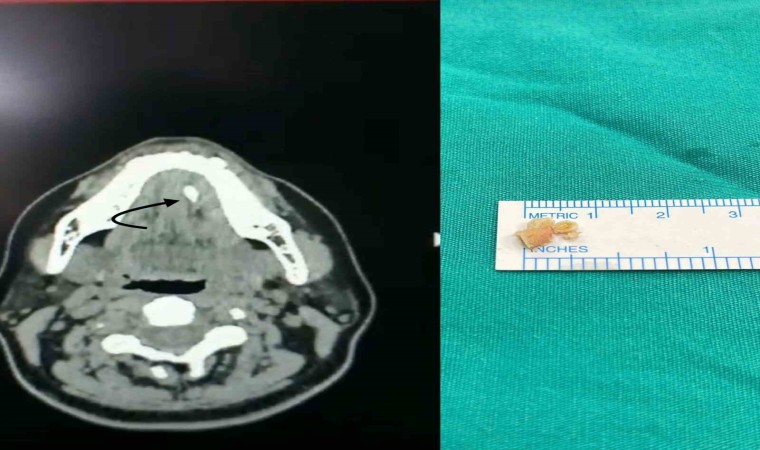

Tükürük bezi taşlarını, çene altında ve yanak arkasında yerleşen tükürük salgısı üreten tükürük bezlerinde veya tükürük bezlerinin ağız içine açılmasını sağlayan tükürük bezi kanallarında görülen taşlar olarak belirten Medicana International Samsun Hastanesi KBB Uzmanı Doç. Dr. Nesrettin Fatih Turgut, “Tükürük bezi taşı tükürük içeriğinin yoğunluğu fazla olduğu için çene altı tükürük bezleri (submandibuler) ve kanallarında ve 30-60 yaş aralığında, erkeklerde daha fazla görülmektedir. Yetersiz sıvı alımı, tükürük salgısının azalmasına neden olan enfeksiyonlar, ilaç kullanımı ve çeşitli enfeksiyonlar ve tükürük bezi kanallarının darlıkları tükürük bezi kanalı içinde taş oluşmasına yatkınlık oluşturur. Bu hastalıkta tipik belirti, taşın var olduğu tarafta yer alan bezde yemek yeme sonrası gelişen şişlik ve ağrıdır. Tükürük salgısının dışarı atılamayıp birikimi, enfeksiyona yatkınlık oluşturur. Bakteriyel tükürük bezi iltihabı dediğimiz hastalık gelişebilir ki bu durumda şikayetler şiddetli hale gelebilir. Etkilenen tükürük bezinin aşırı şişmesi, aşırı hassasiyeti, ağrı ve ateş gelişebilir. Tedavi edilmediği takdirde, hastane yatışı gerektiren ve şiddeti daha fazla olan bir tabloya, derin boyun enfeksiyonuna, ilerleme görebiliriz” dedi.

Şikâyetleri daha hafif olan ve taş boyutları küçük ve tükürük bezi kanalının ucuna yakın yerde yerleşim gösteren hastalarda geleneksel tedaviler önerildiğini dile getiren Doç. Dr. Nesrettin Fatih Turgut, “Ağrı kesiciler fayda sağlar. Bol sıvı tüketimi, ısı uygulaması rahatlama sağlayabilir, bol sıvı tüketimini tüm hastalarımızda önermekteyiz. Aynı zamanda limon gibi ekşi ürünlerin emilmesi tükürük sıvısını artırır ve çok küçük taşların dışarı atılmasını sağlayabilir. Taş boyutunun büyük olması, taşında daha çok beze yakın yerde yerleşmiş olması durumlarında ise cerrahi uygulamaları gündeme gelmektedir. Taş yerleşimi, büyüklüğü etkilenen tükürük bezinin durumu cerrahinin şeklini belirler. Eğer taş tükürük bezi kanalında yer alıyorsa, sialendoskopi olarak adlandırılan kamera sistemi ile yer tespiti ve çıkarma işlemi herhangi bir kesi olmaksızın tercih edilir. Ancak taşın tükürük bezi içerisinde yer alması, boyutunun çok büyük olması durumlarında ise dışardan veya ağız içinden yaklaşım ile cerrahi seçenekleri gündeme gelmektedir” diye konuştu.

Tükürük bezi kanallarının içindeki en uç bölgelere kadar ulaşabilen bir kamera sistemini kullanarak tükürük kanallarını inceleme yöntemi olan sialendoskopiden bahseden Doç. Dr. Turgut, “Bu sistem, kanal içindeki hastalıkların tanısı ve tedavisi için bir araç sağlar. Kamera sisteminin temel özelliği, tükürük kanalının içini milimetrik boyutlarda kontrol etme yeteneğidir, yaklaşık 1.5 mm’lik bir boyuttan bahsedilmektedir. Bu işlem genel anestezi veya lokal anestezi altında uygulanabilir. Hekimin deneyimi, hastanın sağlık durumu, hastanın uyumuna ve tercihine bağlı olarak tedavi planlaması yapılır. Sialendoskopi, genellikle tükürük kanallarında taş olan hastaların tedavisinde kullanılmaktadır. Ayrıca Sjögren hastalığı, radyoaktif iyot tedavisi almış hastalar ve tekrarlayan tükürük bezi iltihaplarına sahip çocuk hastalarda da bu yöntem uygulanabilir. Sialendoskopi süresi, taşın büyüklüğü ve konumuna bağlı olarak değişebilir. Büyük taşlar havalı kırma tekniği kullanılarak küçültülerek çıkarılır, bu nedenle işlem süresi uzun olabilir. Sialendoskopi sırasında herhangi bir kesi veya dikiş uygulanmaz, bu nedenle işlem sonrasında ağrı veya şikâyet gözlemlenmez. Geçici olarak aynı taraftaki tükürük bezinde şişlik olabilir ancak genellikle bu şişlik 1-2 saat içinde azalır. Hastalar, genellikle aynı gün içinde taburcu edilirler” şeklinde konuştu.

Cerrahi müdahale seçeneği hakkında da bilgi veren Turgut, “Taş boyutunun büyük olması, taşın bez içinde yerleşim göstermesi, sık enfeksiyona bağlı taşın kanala yapışık olması gibi nedenlerden dolayı sialendoskopi ile taşın çıkarılması mümkün olmayabilir. Bu durumlarda açık cerrahi seçeneği gündeme gelir. Eğer taş, kanal içinde yerleşim gösteriyorsa ağız içerisinden kanal üzerinde yapılacak ufak bir kesi ile taşa ulaşılır ve taş çıkarılır. Birkaç dikiş atılarak işlem tamamlanır. Hastalarımız ancak taş tükürük bezi içinde olursa veya tükürük bezi sürekli (kronik) enfeksiyona bağlı olarak işlevini yitirmişse (atrofiye uğramış) tükürük bezi genel anestezi altında çene altından kesi yapılarak tamamen çıkarılır. Ameliyat sonrası 2-3 gün hastane yatışı gerekebilir” ifadelerini kullandı.